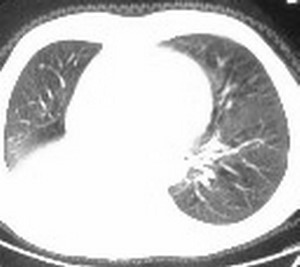

标题: CT6943:[讨论]胸部,M/67Y,体检发现。 [打印本页]

标题: CT6943:[讨论]胸部,M/67Y,体检发现。

1:右侧结核性胸膜炎,胸腔积液;

右肺下叶支气管阻塞,右下叶不张,考虑中心型肺癌伴下叶不张

先考虑:右下肺中心型肺癌伴下叶肺不张、胸腔积液

右肺下叶支气管闭塞,中间段支气管狭窄,下叶不张,胸腔及叶间积液.中心型肺癌伴下叶肺不张.胸腔和叶间积液.

右肺下野后部均匀低密度影,边缘锐利,前缘外突(不支持肺不张),纵隔内未见明显肿大淋巴结,右下肺门结构显示欠清,临床资料太过简单,考虑右侧后胸部包裹性积液。其他待排。建议密切结合临床其他检查。

考虑右下肺中心型肺癌伴下叶肺不张、胸腔积液。